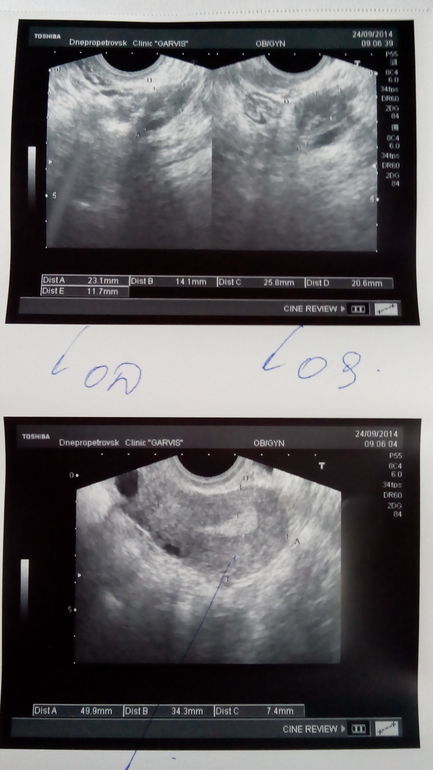

Всем привет!выкладываю вчерашнее УЗИ.Врач назначила мне Дюф с 16 по 25 дц.После того, как заБ, сдать прогестерон, и потом можно перейти на Утрик(если надо будет)

Так уже))) О по тестам была 6 дней назад...Тебе не кажется, что эндик тонковат? Пью утрик на ночь, и все равно не очень...